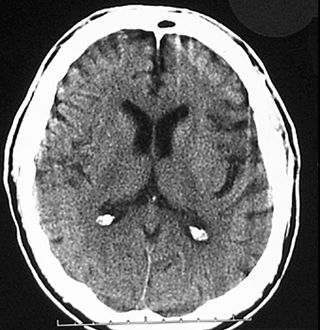

Do you see any abnormality here?